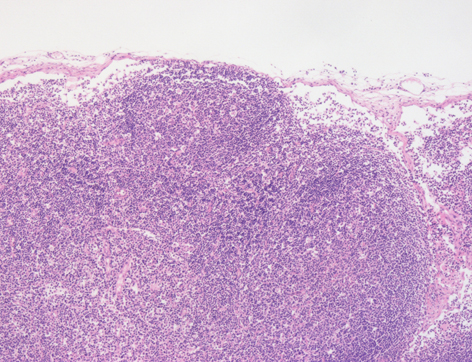

Histológicamente, los ganglios tienen una una cápsula de tejido conjuntivo denso que rodea al órgano y emite trabéculas hacia el interior. Debajo se encuentra el seno supracortical (flecha) que se continúa con los senos corticales, que van paralelos a las trabéculas, los senos paracorticales, localizados bajo los folículos, y los senos medulares (flecha).

El parénquima se diferencia en una zona cortical, una zona paracortical y una zona medular. La zona cortical es más basófila debido al elevado número de linfocitos, los cuales se agrupan en nódulos, los nodulillos linfoides primarios (fp). Éstos, al activarse pueden tener una zona central más pálida debido al menor número de linfocitos, llamada el centro germinal o nodulillo linfoide secundario. La zona paracortical es rica en linfocitos pero no tiene nódulos linfoides. La zona medular está formada por cordones medulares (*) que tienen células plasmáticas, macrófagos y células precursoras, y los senos medulares, tapizados por células endoteliales.

Busca la zona cortical seleccionada para ver los folículos linfoides